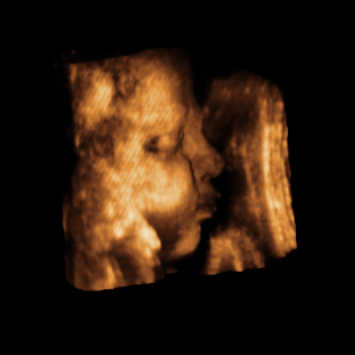

Pompi, szépen kerekedsz, egész sokat nőtt a hasad! Az enyémről nem tudom, mikor tudok képet felrakni, de az nagyon brutál!

Olyan szép, olyan büszke vagyok rá!